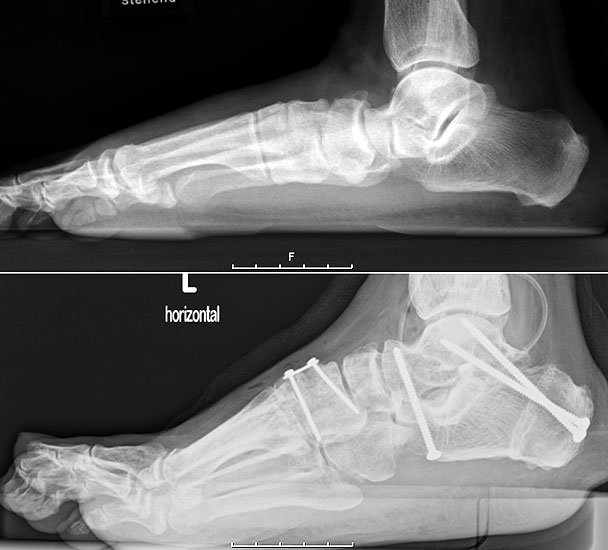

Stehende konventionelle Röntgenbilder eines Fußes mit Planovalgus Deformität Stadium II b dorsoplantar (dp) und seitlich. Auf der dp-Aufnahme zeigt sich die talo-calcaneare Divergenz, der gegenüber dem Kalkaneus nach anterior gleitende Talus und d

Abbildung 5

Stehende Aufnahmen des Fußes dorsoplantar (dp) und seitlich sowie des OSG anteroposterior (ap) sind die Grundlage der konventionellen Röntgendiagnostik (Abb. 5). Ergänzend werden gelegentlich die Rückfuβ-Alignement Aufnahme nach Saltzman 19 und Vergleichsaufnahmen der Gegenseite durchgeführt.

Radiologisches Beispiel einer fixierten Planovalgus Deformität Stadium III, 51 jähriger Patient. Stehendes präoperatives Röntgenbild und 1 Jahr postoperatives Röntgenbild des Fußes seitlich. Die Korrektur der Deformität umfaßte eine leicht korrigierende U

Abbildung 12

Im Stadium III der Tibialis posterior Sehneninsuffizienz bei fixierter Deformität und/oder erheblich eingeschränkter Inversion im USG aber stabilen und flexiblen Chopart-Gelenk und weniger als 10° fixierter Vorfußsupination eine in-situ oder leicht korrigierende USG-Arthrodese indiziert. Der Vorteil einer isolierten USG-Arthrodese gegenüber einer Triple- oder Double-Arthrodese ist die verbleibende, funktionell wichtige Beweglichkeit in der Chopart-Gelenkreihe. Um einem persistierenden fibulocalcanearem Impingement sicher vorzubeugen, sollte die USG-Arthrodese in maximal 5° Valgus- oder sogar Neutralposition erfolgen. Zur Prophylaxe eines Rezidivs wird die USG-Arthrodese zudem häufig mit einer medialisierende Tuber calcanei Osteotomie und / oder einem FDL-Transfer kombiniert (Abb. 12).